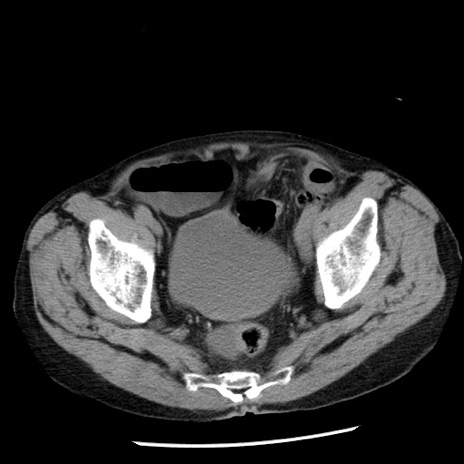

症例26(横断像)

【症例】80歳代男性

【主訴】嘔吐

【現病歴】昨晩2回嘔吐あり、今朝になっても嘔吐あり。来院。

【既往歴】胃潰瘍

【身体所見】意識清明、BT 37.6℃、BP 166/95mmHg、HR 100bpm、SpO2 97%、腹部:平坦・軟、腸蠕動音聴取良好、圧痛なし。

【データ】WBC 21900、CRP 1.46